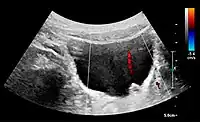

![]() Doppler ultrasound (US) of a normal adult kidney with the estimation of the systolic velocity (Vs), the diastolic velocity (Vd), acceleration time (AoAT), systolic acceleration (Ao Accel) and resistive index (RI). Red and blue colors in the color box represent flow towards and away from the transducer, respectively. The specrogram below the B-mode image shows flow velocity (m/s) against time (s) obtained within the range gate. The small flash icons on the spectrogram represent initiation of the flow measurement.[1] | |

Doppler ultrasonography of the kidney is widely used, and the vessels are easily depicted by the color Doppler technique in order to evaluate perfusion. Applying spectral Doppler to the renal artery and selected interlobular arteries, peak systolic velocities, resistive index, and acceleration curves can be estimated (Figure 4) (e.g., peak systolic velocity of the renal artery above 180 cm/s is a predictor of renal artery stenosis of more than 60%, and a resistive index, which is a calculated from peak systolic and end systolic velocity, above 0.70 is indicative of abnormal renovascular resistance).[1]